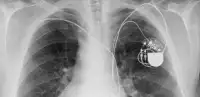

Today, minimally invasive interventional medicine has developed and includes coronary angioplasty to treat blockages in the coronary arteries around the heart. Today over 75,000 coronary angioplasties are carried out annually in the UK alone, providing potentially life-saving treatment for hundreds of people daily. Dr Dotter and Bill Cook’s innovative approach opened up a dawn of new possibilities for radiologists and transformed the medical community’s approach to cardiovascular surgery.